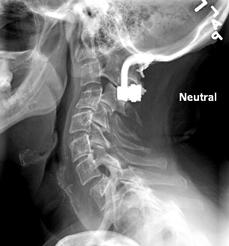

Plain film of C-spn 15 years post decompression of foramen magnum, placement of a bovine (cow) pericardium sling for ACM, and titanium rod fusion of occiput to C3 (C4 ?)  -  PRE odontoid removal.

My original MRI -   NO clivus. Third cervical vertebra is now at the level of rounded white bone on first picture.  C1 and C2 are way up inside skull and jagged top is offending the brain stem. Initial brainstem width measured 18mm. ACM obscured by artifact from titanium.